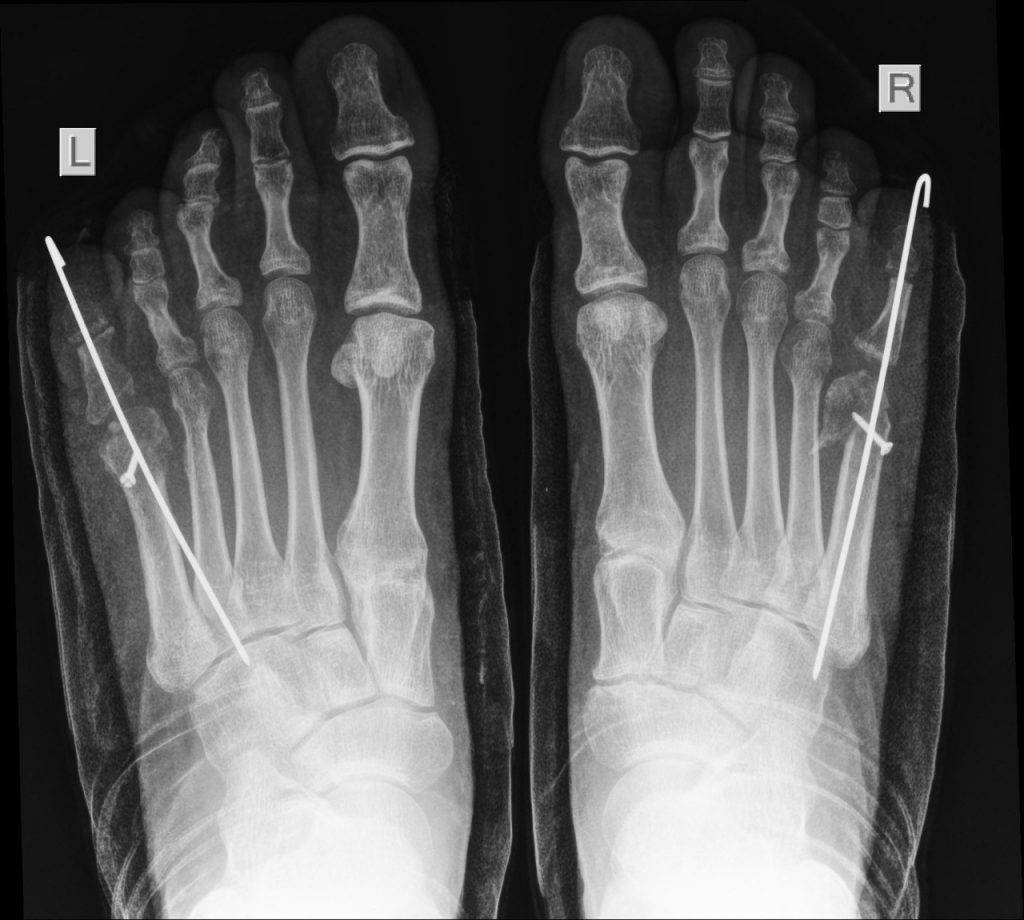

ENLARGEMENT OF THE FIFTH METATARSAL

I recently had the privilege of seeing a patient with an interesting enlargement of the fifth metatarsals of both feet. The problem was not so much pain as difficulty with shoewear.

I elected to shorten the metatarsals and stiffen the proximal joint of the little toes so the form of the foot could approach normality.